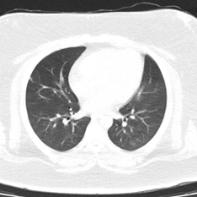

入院血常规提示白细胞、中性粒细胞正常。肝功能示谷丙转氨酶154U/L,谷草转氨酶65U/L,总胆红素8.4μmol/L。胸部CT提示双肺可见散在斑片状磨玻璃密度影,以胸膜下为著(图2-3-63)。西医诊断:新型冠状病毒肺炎。

图2-3-63 2020年2月18日胸部CT